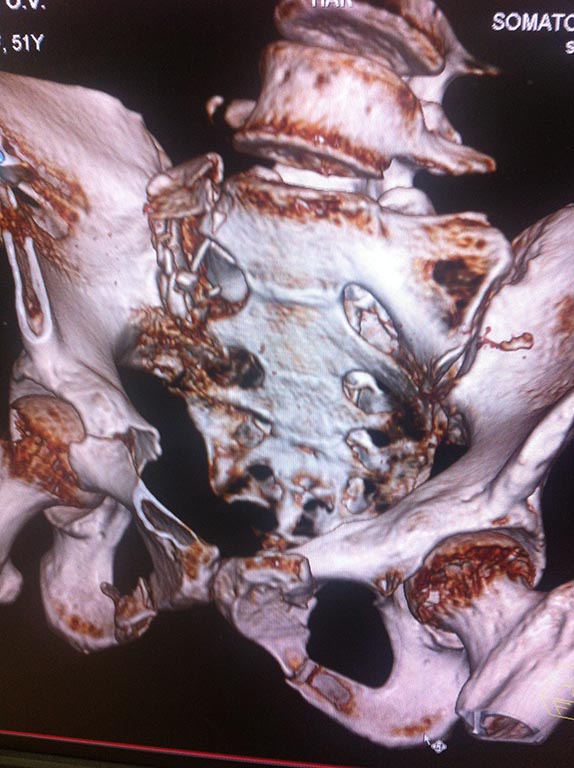

Женщина 51 год, травма в ДТП. Неврология незначительна справа, заключается в иррадиации болей по задней поверхности бедра. Движения в суставах правой нижней конечности не ограниченны.Но картина КТ заставляет задуматься? Что посоветуете?

Я так понимаю по КТ, что АНФ наложен?

Может есть смысл немного "открыть книгу", раздвинув стержни аппарата между собой и повторить КТ - есть шанс уменьшить компрессию на корешки и продолжить лечение в аппарате (это так, малой кровью)

Если не будет положительной динамики лечения "неврологии", очевидно, декомпрессирующая ламинектомия крестца справа + МОС пластиной или 2 спонгиозными винтами с цельной резьбой